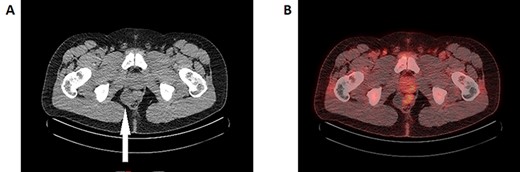

A 37-year-old gentleman was referred to see a general surgeon with a 4-week history of right groin pain on a background of a previous right inguinal hernia repair. He was otherwise well with no major systemic comorbidities. A computed tomography (CT) scan of the abdomen and pelvis had been organized, which did not demonstrate an abdominal wall defect. Incidentally, there was a 3 cm lobulated cystic mass below the perineal floor on the right side abutting the rectal wall (Fig. 1A). He denied any symptoms of perineal pain or alteration on bowel habit. On examination, his abdomen was benign with no groin cough impulse felt bilaterally. Digital rectal examination (DRE) was normal with no palpable mass.

A: Axial slice of the CT pelvis demonstrating a cystic structure in the right presacral space adjacent to the rectum (white arrow). B: FDG-PET/CT reconstruction imaging demonstrating the same cystic lesion adjacent to the FDG-avid rectum. The medial end of the cyst demonstrates FDG-avidity, though it is unclear whether this is intrinsic or artefact from the neighbouring rectum.

A magnetic resonance imaging (MRI) was performed demonstrating a multiseptated perianal cystic collection on the right side ~3 cm from the anal verge extending craniocaudally (Fig. 2A–C). The working diagnosis at the time was a complex congenital cyst. A thin rim of T2-hypointense material was present on its medial wall indicating a solid component, which raises the possibility of malignant potential (Fig. 2B) [3]. A fluorodeoxyglucose (FDG)-positron emission tomography (PET) scan was performed accordingly and while the majority of the cyst was poorly FDG avid, the solid component was difficult to assess due to surrounding artefact from the adjacent rectum (Fig. 1B). The decision was made to proceed with surgical excision.